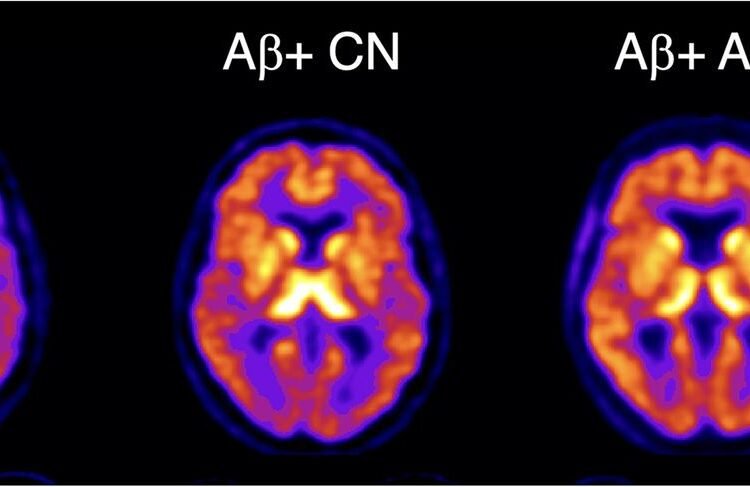

The three clinical groups were then classified based on their Ab status (either as Ab+ or Ab-). No significant differences in 18F-SMBT-1 binding were found among Ab- participants in the control and MCI groups. In the Ab+ subjects with Alzheimer’s disease, 18F-SMBT-1 binding was significantly higher. Most importantly, 18F-SMBT-1 binding was significantly higher in the Ab+ control group as compared to Ab- control group.

“It’s of note that the brain regions where we saw this higher 18F-SMBT-1 binding in the control group are regions known for early Ab deposition. This suggests that reactive astrocytes are associated with early Ab deposition at the preclinical stages of Alzheimer’s disease and likely play a role over clinical progression,” said Villemagne.